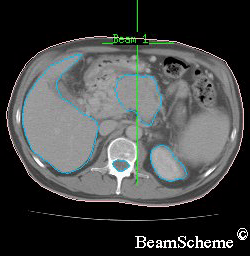

An example of a scan

X-rays show your bones in the treatment area. And scans show the size, shape and position of the cancer as well as the surrounding tissues and bones.